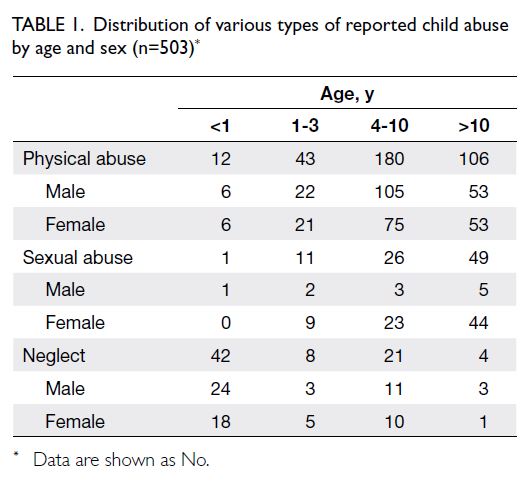

In total, 503 reported cases of child abuse were

included in the study. The number of reported cases

showed an upward trend over the 10-year period,

from 23 cases in 2014 to 50 cases in 2023 (Fig 2).

The case distribution is presented in Table 1.

The cohort comprised 265 (52.7%) girls and 238

(47.3%) boys. The mean age was 8.25 years (range,

0-17), with 55 cases (10.9%) involving infants

under 1 year of age. Physical abuse was the most

common type at presentation, accounting for 341

cases (67.8%). The vast majority (>99%) of patients

presented with erythematous marks, bruises, or

lacerations. Other presenting symptoms included

seizures, loss of consciousness, and vomiting. Sexual

abuse was the second most common type (n=87,

17.3%), followed by child neglect (n=75, 14.9%).